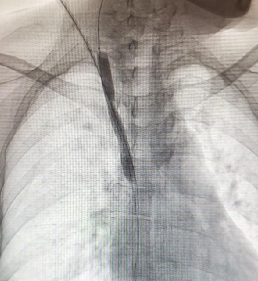

肾脏内科龚蓉主任带领团队回顾病史发现,李阿姨已经使用原半永久血透导管进行血液透析3年有余,近半年透析不时会出现导管流量下降、透析效率不达标等情况,考虑存在透析导管所致中心静脉病变,传统方式重新置管风险高、难度大,肾内科林新强主治医生与放射介入科刘武军主任联合为患者制定了个性化的手术方案,在数字减影血管造影(DSA)引导下见患者的右侧颈总静脉与右锁骨下静脉汇合部及上腔静脉起始部狭窄,使用10mm球囊扩张后狭窄病变明显改善,血流恢复通畅,并顺利置入新的半永久血透导管。

(球囊扩张前造影)